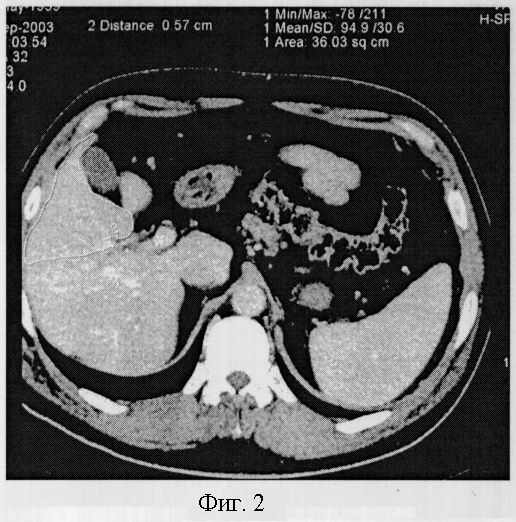

Пример 4. Гипоплазия 2 степени.

Больная Головач Л.И. 54 лет, направлена компьютерно-томографическое обследование с подозрением на опухоль печени. При исследовании отмечается некоторое увеличение объема печени, преимущественно за счет левой доли. Объем печени составил 1584,3 см3, объем правой доли – 295,8 см3. Печень расположена нормопетально, поверхность печени гладкая, контур в области расположения 6 и 7 сегментов деформирован. Структура паренхимы однородная, плотность 63 HU. Изменение объема правой доли обусловлено уменьшением объема 5-8 сегментов, объем которых варьировал от 69,3 до 71,6 см3, а коэффициент К=0,29 и 0,28, что соответствовало гипоплазии 2 степени. Диаметр сегментарных ветвей правой доли был уменьшен неравномерно и варьировал от 0,51 в восьмом сегменте до 0,49 в пятом (фиг.4).